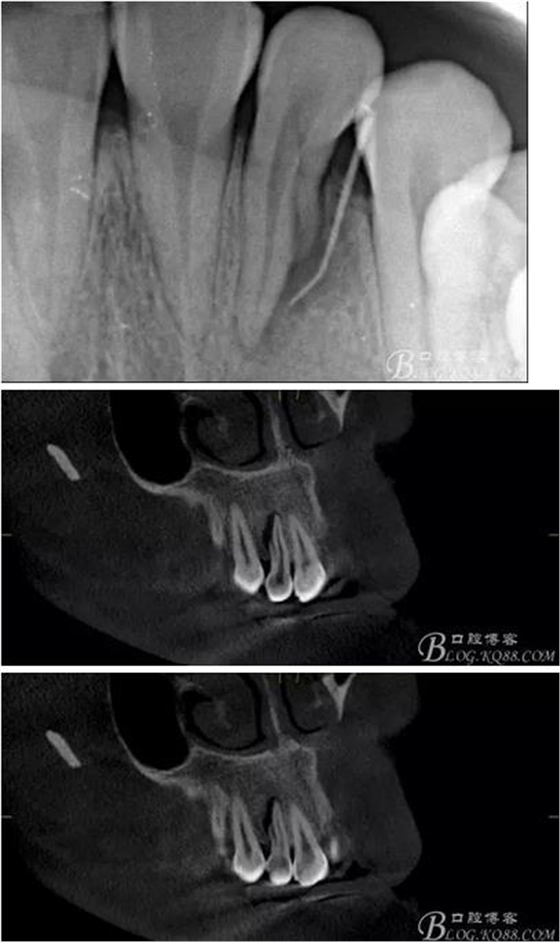

(1)檢查:12唇側(cè)牙齦可見竇道,牙體顏色較鄰牙暗,無光澤,形態(tài)完整無缺損,唇側(cè)及近遠(yuǎn)中向未提及牙周袋。腭側(cè)齦緣輕度紅腫,舌側(cè)窩可探及裂溝,可見浸墨狀痕跡,沿裂溝舌側(cè)探診牙周袋深大于11mm,除患牙外全口牙周狀況良好,為探及牙周袋,牙齦色粉紅。邊緣菲薄,質(zhì)地堅韌。12冷熱診無反應(yīng),叩診(+-),無明顯松動,無咬合創(chuàng)傷。12根尖x線片示,根管中三分之一中可見一斜向線樣透射影像根尖區(qū)及遠(yuǎn)中根三分之一可見低密度透射暗影,錐形束CT示12根尖區(qū)唇腭向骨吸收已穿通,根面溝達(dá)根中三分之一卷曲分出另一牙根,再未見其他明顯的根管系統(tǒng)。

(6)復(fù)診:原暫封材料再位,牙周無明顯異常與不適,常規(guī)清潔根管,H銼清除根管內(nèi)維他,次氯酸鈉終末消毒,干燥根管,單尖測壓發(fā)充填根管,術(shù)后拍片到位。